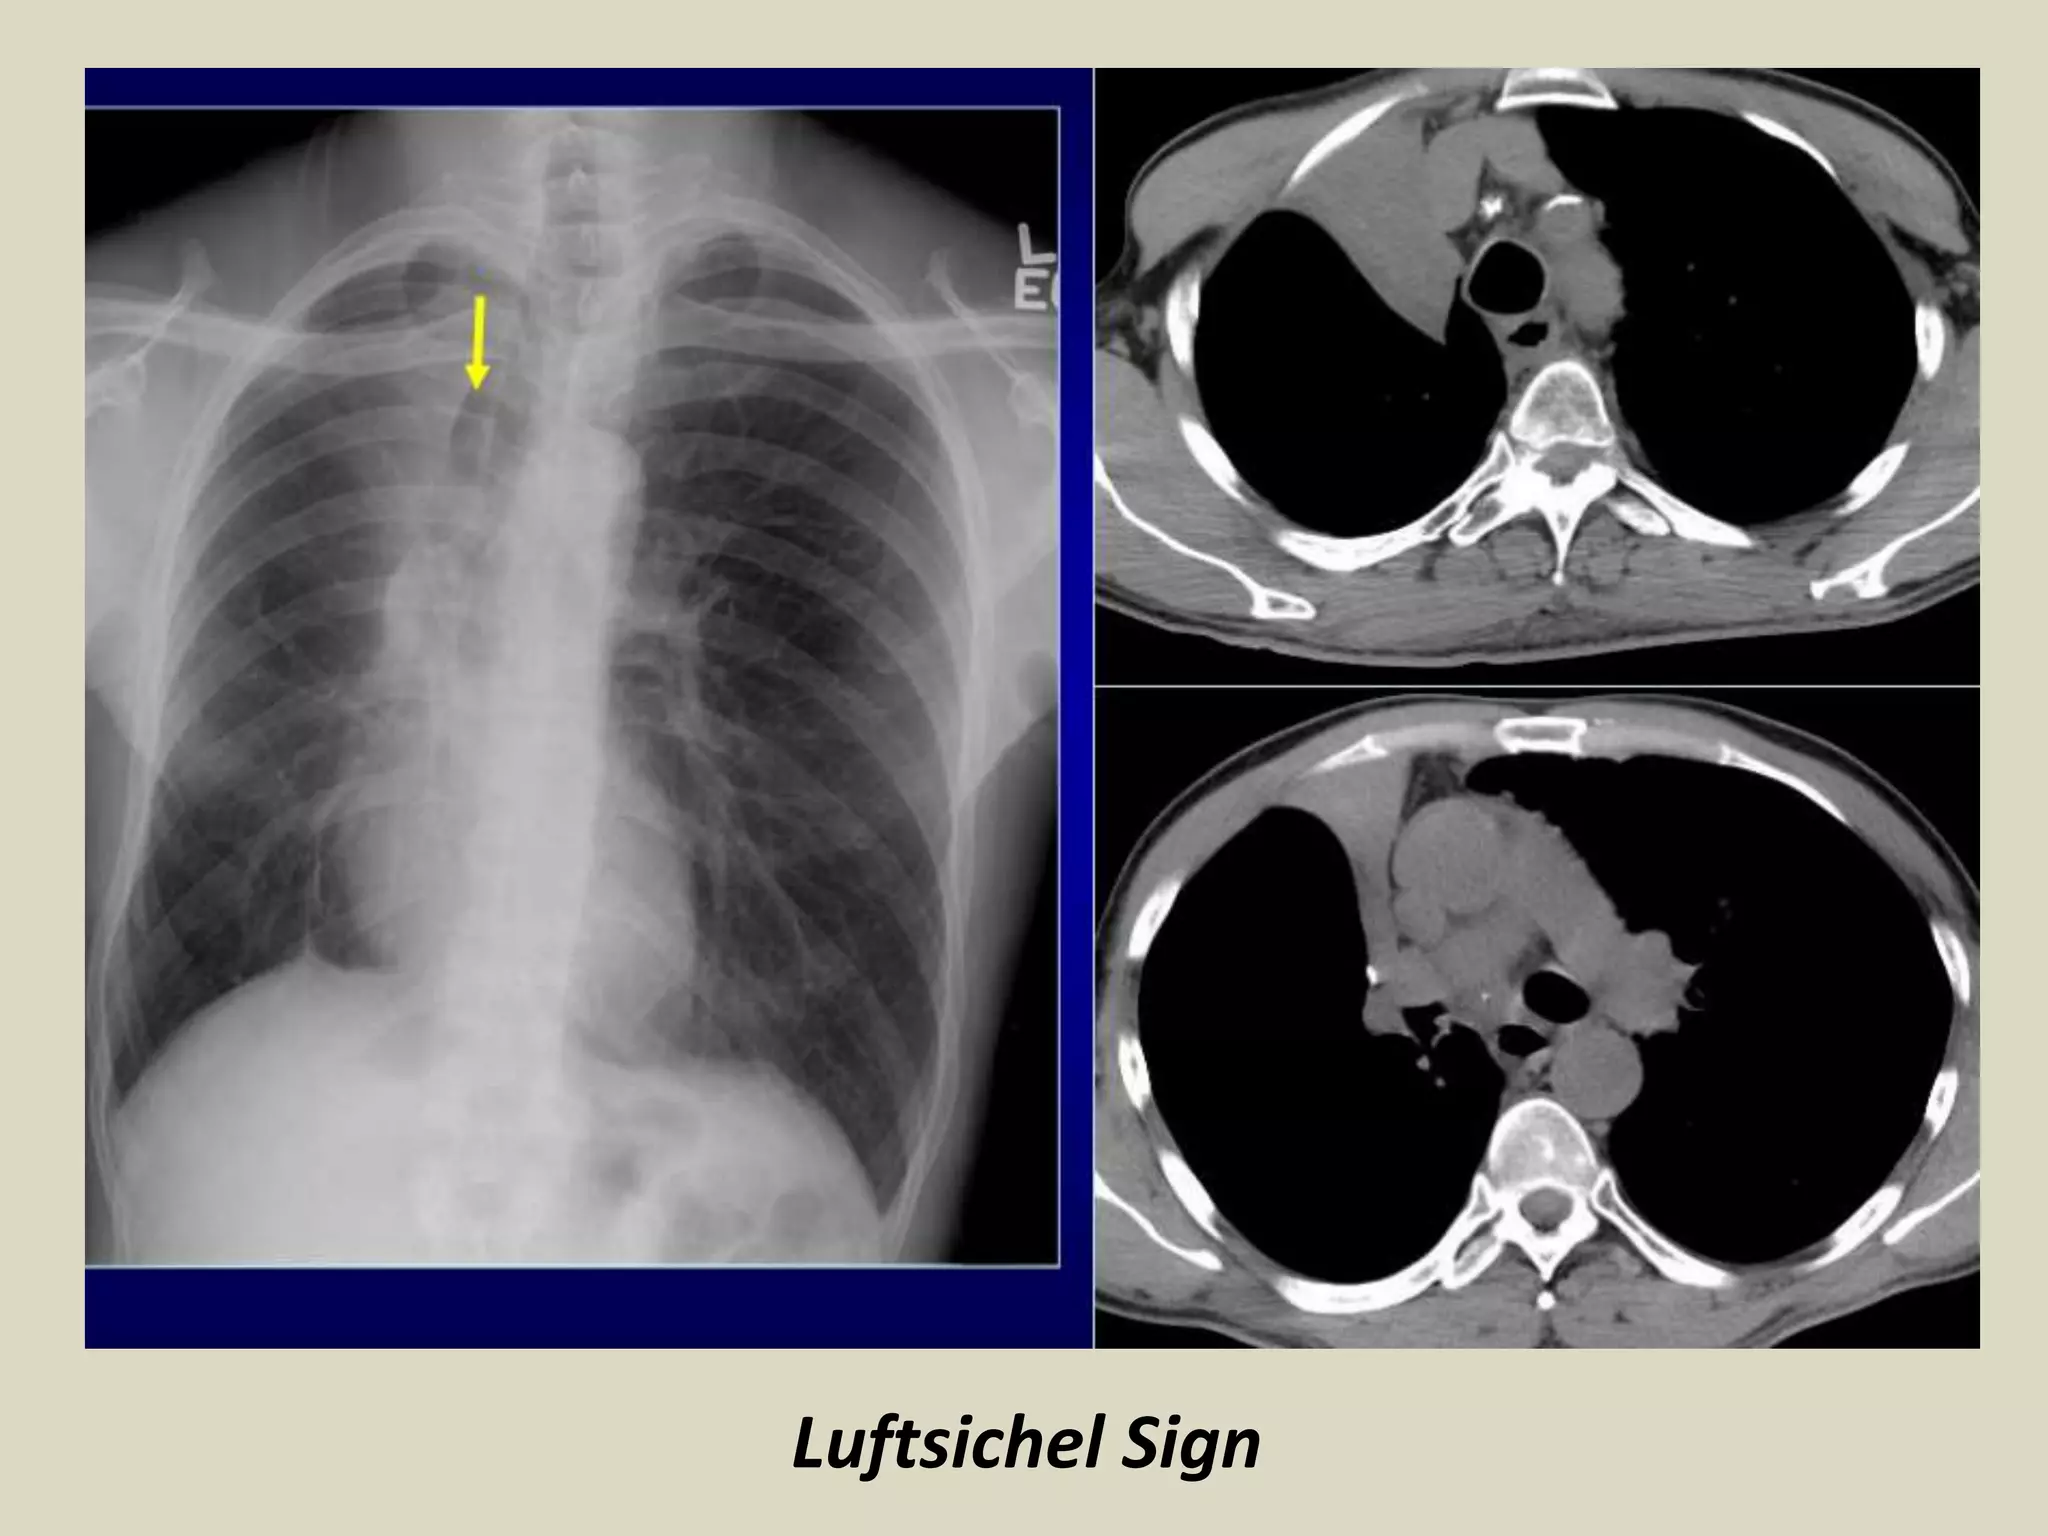

Luftsichel Sign

• German for sickle of air (luft: air sichel: crescent)

• Para-mediastinal lucency due to interposition of lower lobe

apex between mediastinum and shrunken upper lobe

• Occurs more commonly on the left than in the right

Luftsichel Sign • Germanfor sickle of air (luft: air sichel: crescent) • Para-mediastinal lucency due to interposition of lower lobe apex between mediastinum and shrunken upper lobe • Occurs more commonly on the left than in the right